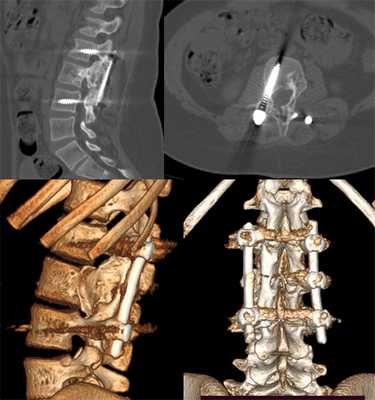

Показаниями к хирургическому вмешательству являются:

выраженная угроза развития стеноза позвоночного канала, обширное разрушение позвонка;

кисты, занимающие более 2/3 поперечного сечения кости;

стойкие боли, неврологический дефицит;

отсутствие эффекта от проводимой в течение 6—8 месяцев консервативной терапии;

Сама операция выполняется открытым путем под общей анестезией. Она заключается в удалении новообразования вместе с капсулой и проведении электрокоагуляции стенок кисты. В результате в позвонке остается полость, которую заполняют собственной костью пациента или другим материалом.

Если образование имеет крупные размеры, дополнительно требуется установка фиксирующих систем. Они стабилизируют прооперированный позвоночно-двигательный сегмент, исключают риск смещения и дополнительно укрепляют позвонок.

В случаях развития неврологических осложнений удаления только кисты бывает недостаточно. В рамках хирургического вмешательства обязательно проводят ревизию и декомпрессию нервных структур. Как правило, для этого применяются микрохирургические техники, обеспечивающие хороший доступ к позвоночнику и при этом позволяющие избежать образования крупных косметических дефектов.